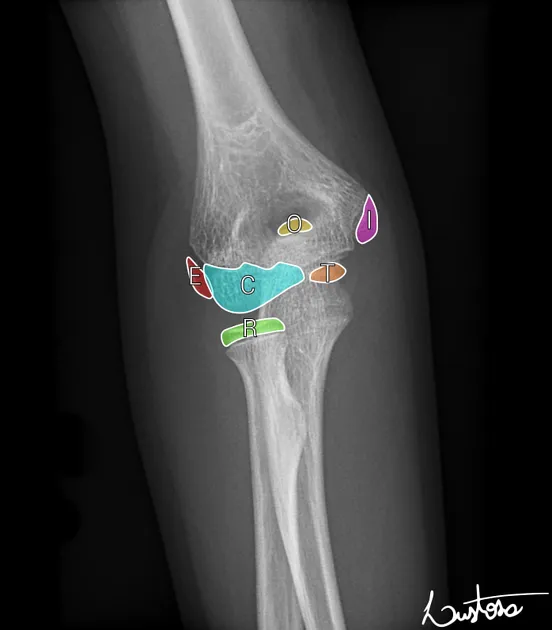

- Ossification Centers: Primary (diaphysis), Secondary (epiphysis). Appearance/fusion age varies (e.g., elbow: CRITOE š).

- Order of elbow ossification: Capitellum (1yr), Radial head (3yr), Internal (medial) epicondyle (5yr), Trochlea (7yr), Olecranon (9yr), External (lateral) epicondyle (11yr).